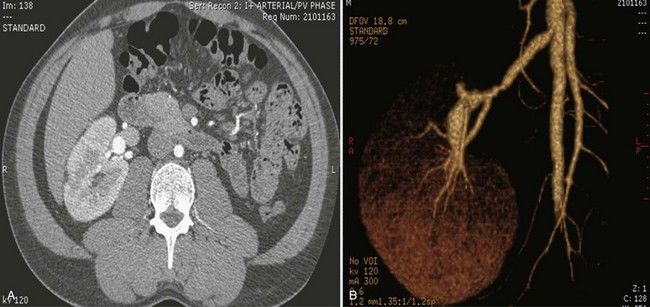

Frequent anatomic variation in the renal vasculature contributes to the complexity of open renal surgery. Multiple renal arteries, which typically arise from the aorta or iliac arteries, are the most common variation, occurring in 25% to 30% of the population (Merklin and Michels, 1958; Boijsen, 1959; April, 1997). Supernumerary hilar renal arteries originate at the aorta adjacent to the renal artery and traverse the renal hilum, whereas polar renal arteries originate at a greater distance from the main renal artery and enter the renal parenchyma directly. Ectopic and horseshoe kidneys more frequently have supernumerary renal arteries (Fig. 54–11).

Figure 54–11 Horseshoe kidney with multiple arterial branches well defined with three-dimensional imaging.